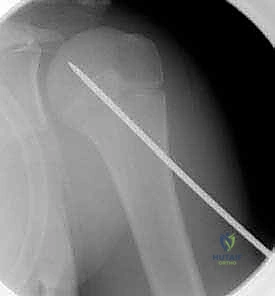

الرد المغلق والتثبيت بأسلاك كيرشنر عبر الجلد (CRPP):

هذه التقنية هي المفضلة في الكثير من كسور عظم العضد القريب. يتم إرجاع العظم إلى مكانه الصحيح تحت جهاز الأشعة السينية المتحرك (C-arm) في غرفة العمليات دون فتح الجلد. ثم يتم إدخال أسلاك معدنية رفيعة جداً (K-wires) عبر الجلد لتثبيت الكسر. تُترك نهايات الأسلاك خارج الجلد ليتم سحبها بسهولة في العيادة بعد 3-4 أسابيع دون الحاجة لعملية أخرى. -